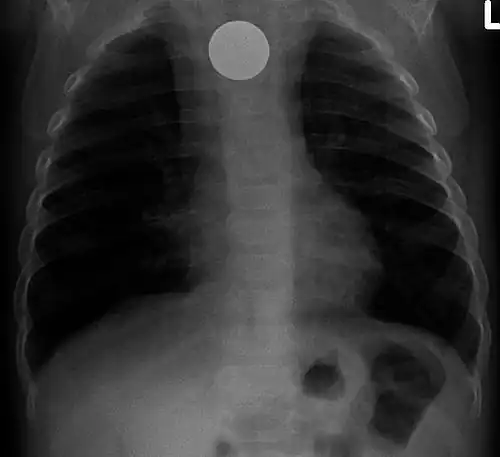

Multiple button batteries in the stomach -

Button battery in the stomach

Both children and adults experience problems caused by foreign objects becoming lodged within their bodies. Young children, in particular, are naturally curious and may intentionally put shiny objects, such as coins or button batteries, into their mouths. They also like to insert objects into their ear canals and nostrils.[1] The severity of a foreign body can range from unconcerning to a life-threatening emergency. For example, a coin causes local pressure on the tissue but generally is not a medical emergency to remove. A button battery, which can be a very similar size to a coin, generates hydroxide ions at the anode and causes a chemical burn in two hours.[2] An ingested button battery that is stuck in the esophagus is a medical emergency. In 2009, Avolio Luigi and Martucciello Giuseppe showed that although ingested nonmagnetic foreign bodies are likely to be passed spontaneously without consequence, ingested magnets (magnetic toys) may attract each other through children's intestinal walls and cause severe damage, such as pressure necrosis, perforation, intestinal fistulas, volvulus, and obstruction.[3]